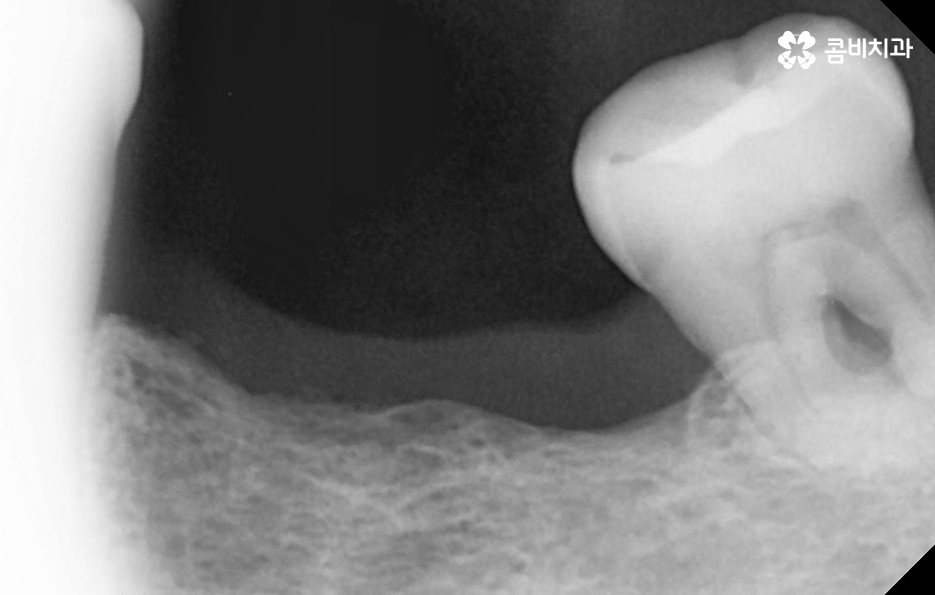

그 중에서도 치주염으로 인해 위에 보시는 사례 사진처럼 잇몸은 내려앉고 치아 뿌리가 외부에 상당 부분 드러나는 경우에는 우선 일상에서 치아가 무척이나 시리고 통증을 느끼게 되며 치주염이 결국 잇몸 뼈를 녹게 만들어서 치아 뿌리가 흔들리고 결국 발치하게 되는 경우가 많아요

치주염은 충치 이상으로 치아를 상실하게 만드는 대표적 원인이며 치주염은 주변 잇몸 뼈에도 악화되고 잇몸 뼈를 녹인다는 점에서도 임플란트를 해야할 시점이 되면 잇몸 뼈의 부족으로 인한 뼈이식을 받게 되는 경우가 많을 거예요